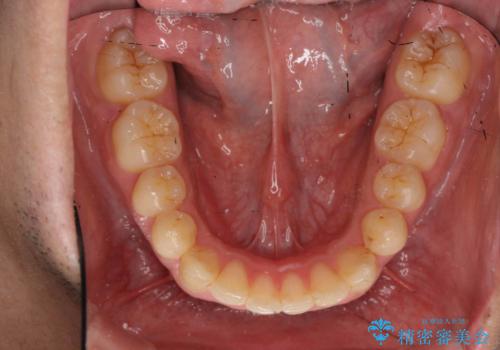

歯を抜かない矯正 奥歯のすれ違い咬合 下の八重歯

- 前歯のガタガタを主訴に来院。

奥歯はすれ違ってしまっていました。

口元も出ておらず、非抜歯を希望されたため、IPR(歯を削る処置)でスペースを確保しました。

上顎両側7番(一番奥の歯)はすれ違っており、虫歯になっていました。